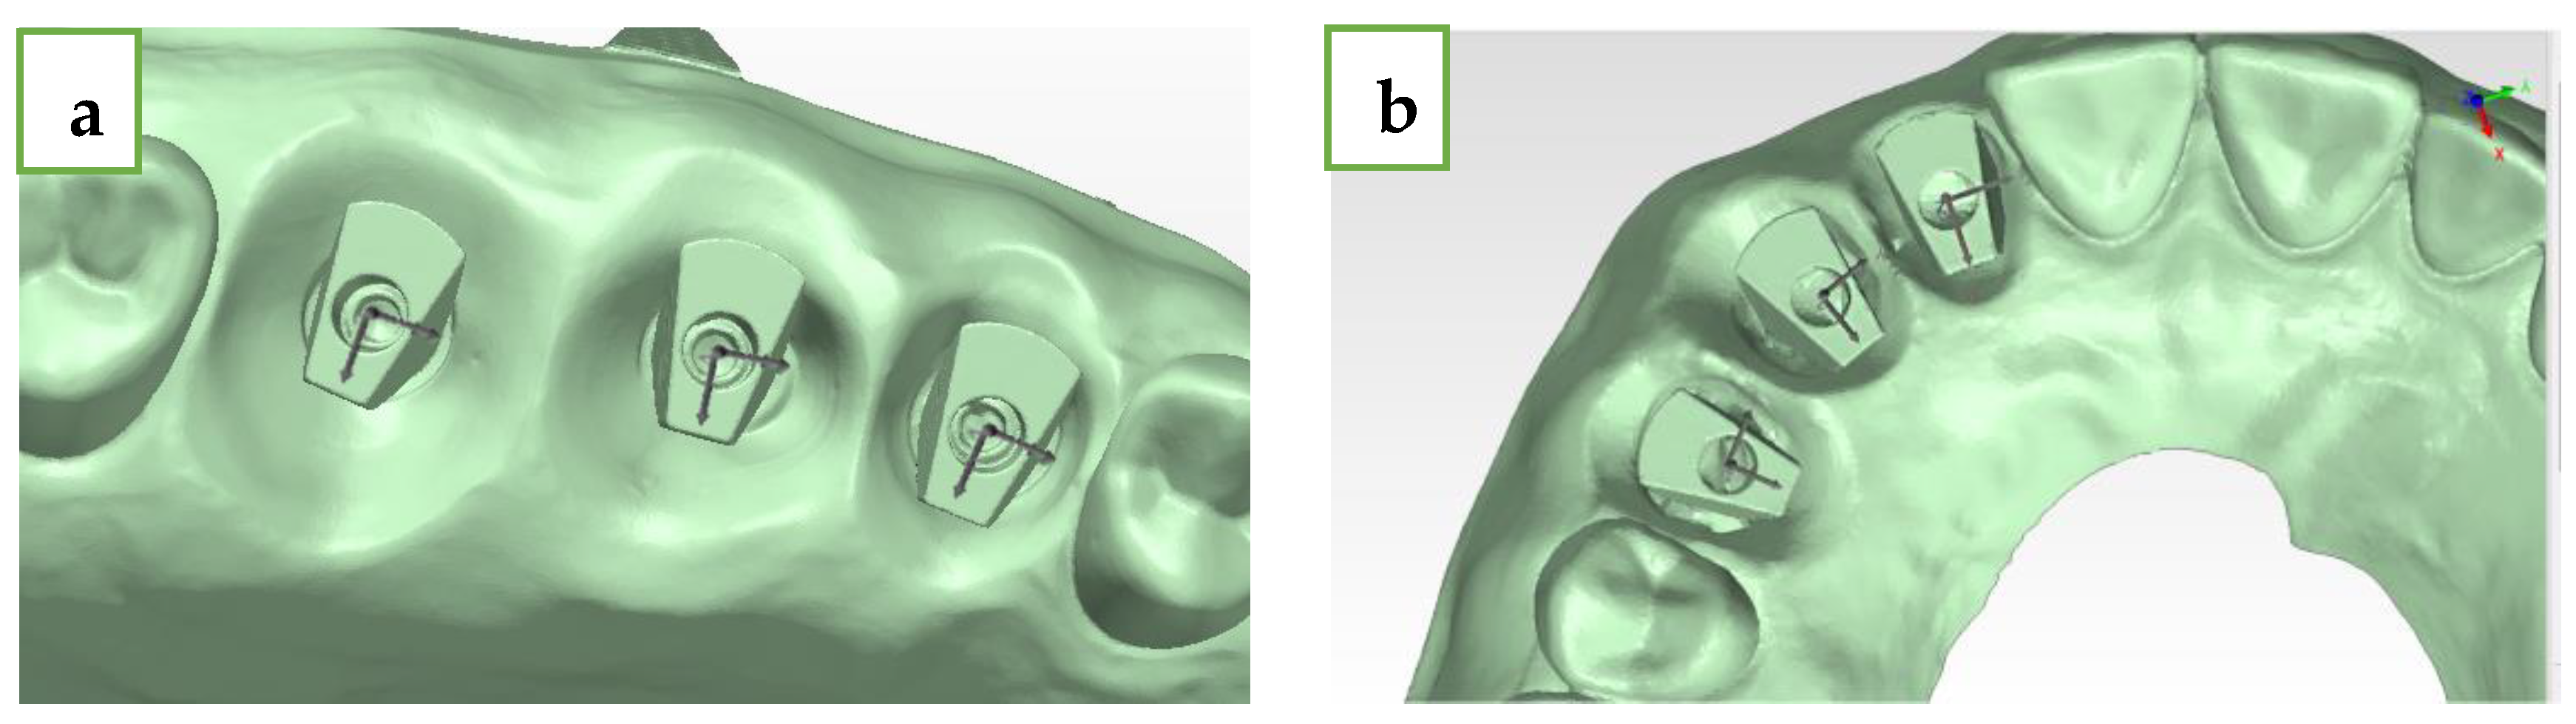

- Delta axis 1–2 (green)—defined as the angle formed between the axis of the mesial (#15 and #12) and middle (#16 and #13) MIS ISB;

- Delta axis 2–3 (orange)—defined as the angle formed between the axis of the middle (#16 and #13) and distal (#17 and #14) MIS ISB;

- Delta axis 1–3 (blue)—defined as the angle formed between the axis of the mesial (#15 and #12) and distal (#17 and #14) MIS ISB.